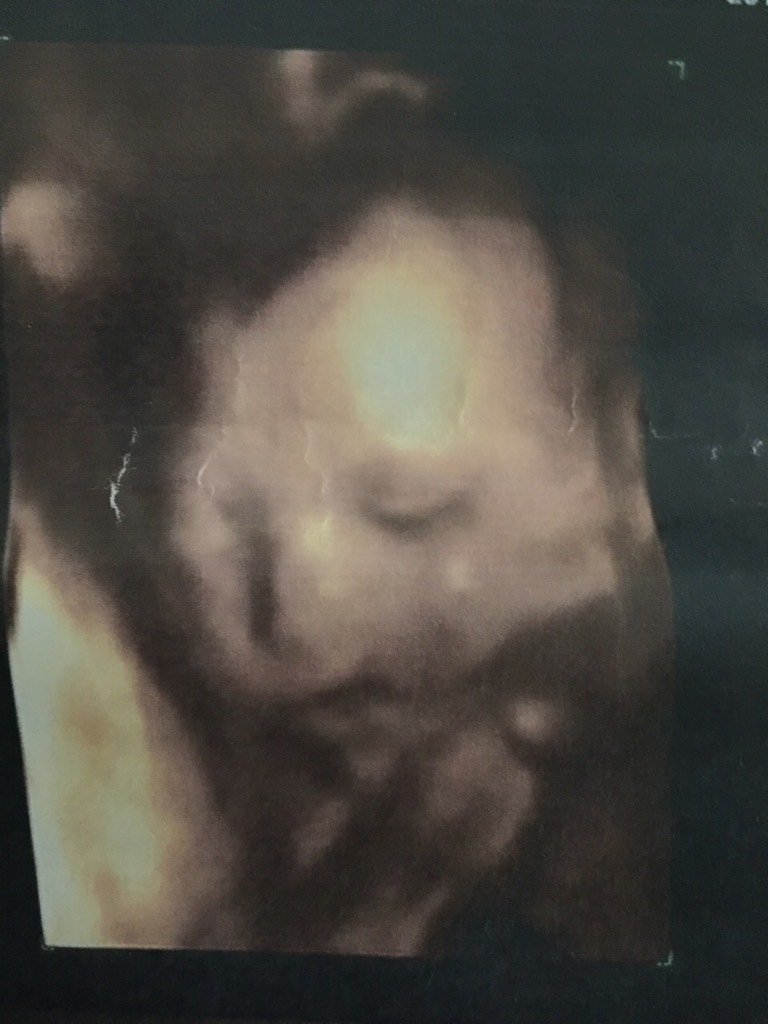

楼主

萌神小Baby

宝宝9岁9个月6天 LV.7因为我的羊水偏少,肚子里还有胀气有泡泡,所以照的模糊。完整健康就满足啦~

雪儿妈咪斌仔爸比:好模糊呀 我家照的很清晰

宝宝9岁9个月6天 LV.73.7cm

゛阳光下、为谁回眸_btFE:宝妈羊水现在多少